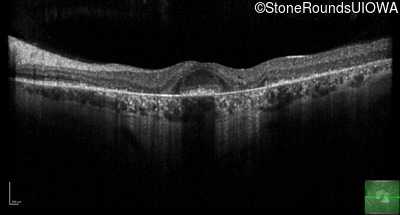

Optical Coherence Tomography - Right - 20/32 +2

Exemplar / OCT Stack